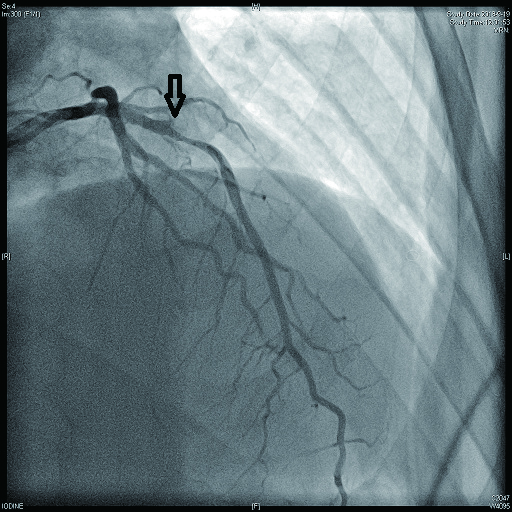

病例1 1 LAD近段(图 9 75%~90% 2级 LAD近段植入支架1枚

图 9 病例1冠脉造影示LAD近段病变